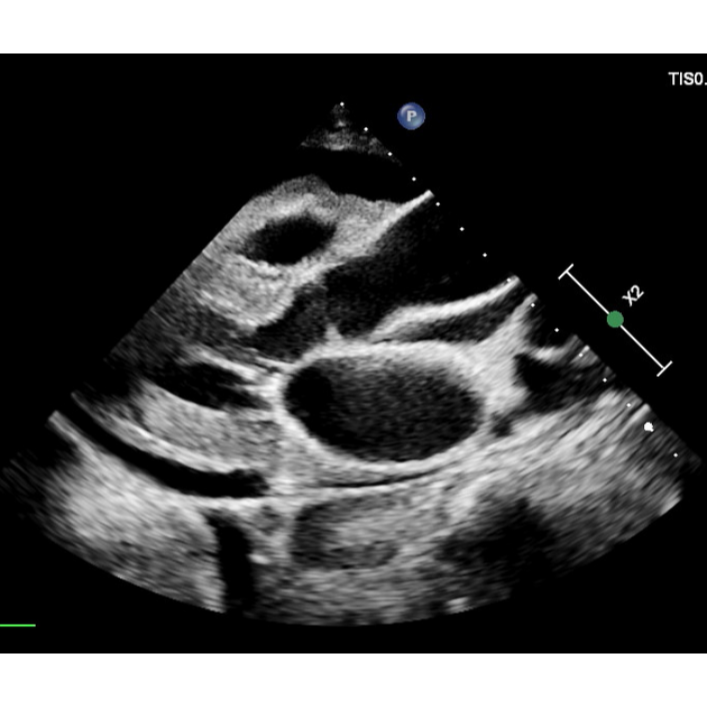

best heart clinics in yelahanka Pericardial effusion is a serious medical condition where excess fluid accumulates in the pericardial sac—the double-layered sac that surrounds the heart. This buildup of fluid puts pressure on the heart, impairing its ability to pump blood effectively and potentially leading to cardiac tamponade, a life-threatening complication. Causes range from infections and autoimmune diseases to heart conditions, trauma, and cancer.